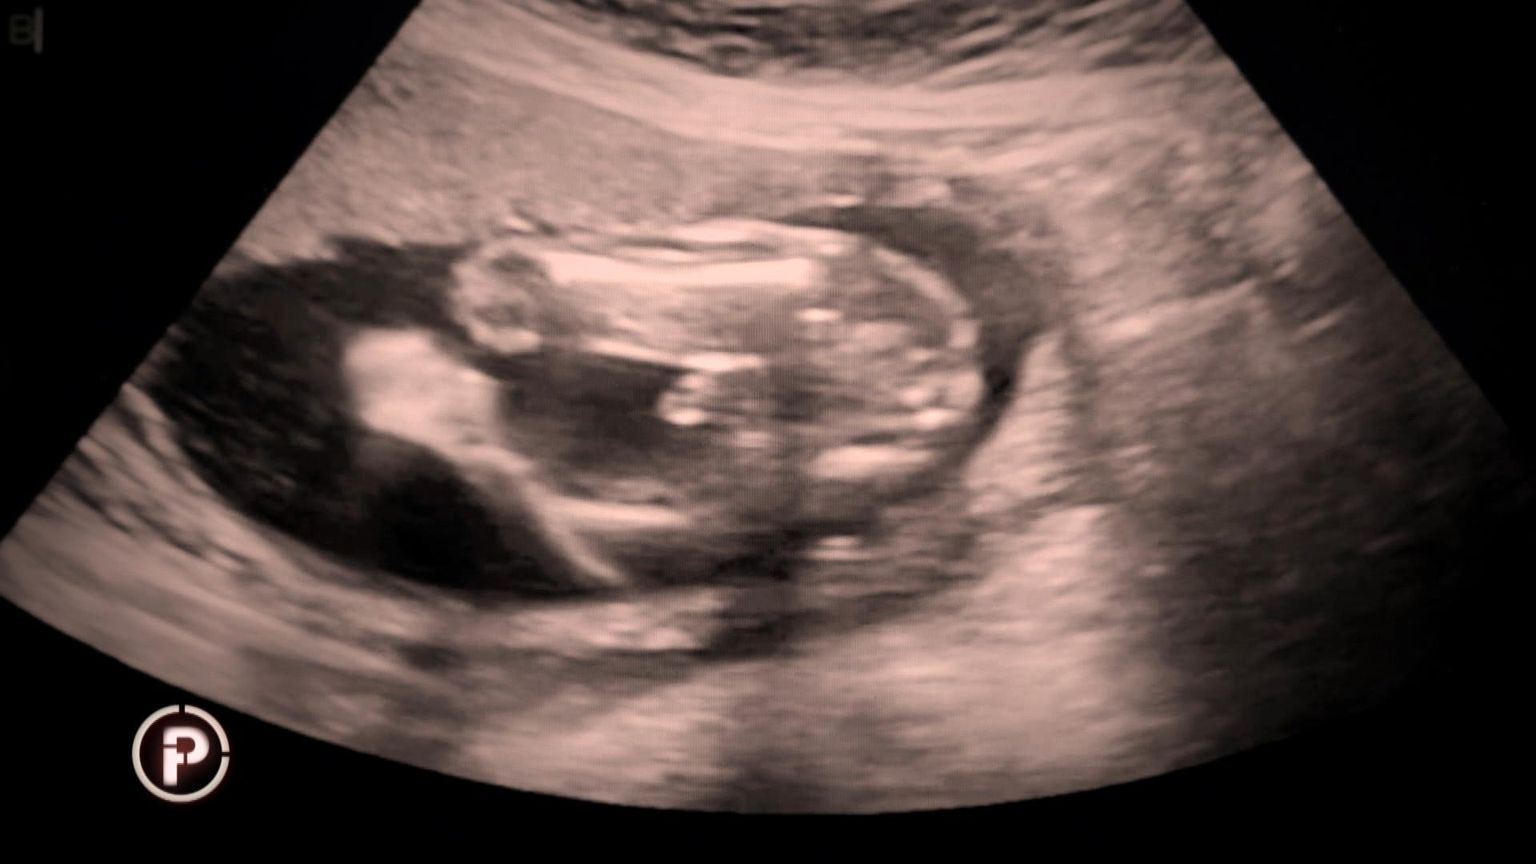

Šokantan slučaj iz Rijeke: "Udahnula sam, napravila korak naprijed i pogledala ga. Kao da fali pola mene. Prazan zagrljaj. Ja sam mama bez djeteta...''

• Provjereno otkriva skandalozan slučaj iz riječkog KBC-a - 9 Foto: Provjereno